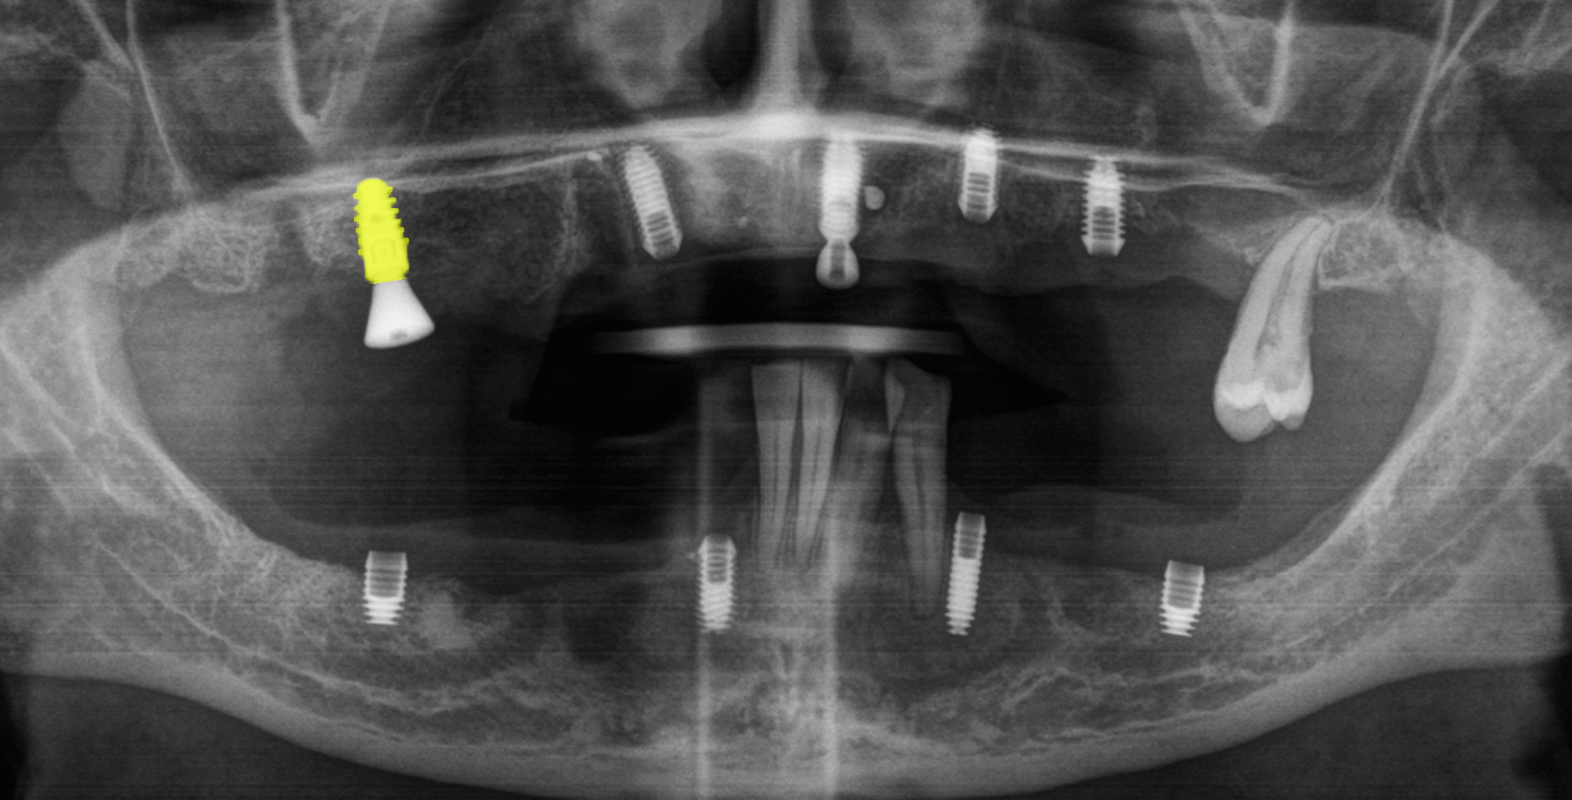

- Зубы 4.1, 3.1, 3.2, 3.3 удалить в связи с подвижностью этих зубов первой и второй степени

После консультации врача-парадонтолога пациентка все же приняла решение удалить зубы нижней челюсти в связи с высоким риском потери зубов и, как следствие, риском необходимости нового зубного протеза для нижней челюсти.